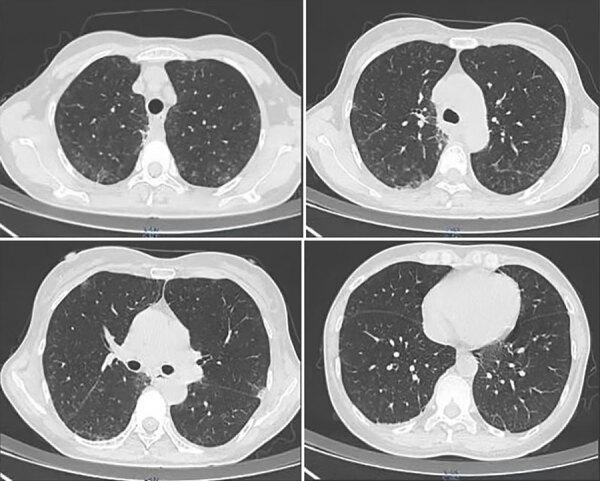

Pneumocystis jirovecii pneumonia is an opportunistic infection that affects HIV-infected and immunocompromised persons and rarely affects immunocompetent patients. However, after the advent of the COVID-19 pandemic, some COVID-19 patients without immunocompromise or HIV were infected with P. jirovecii. Clinical manifestations were atypical, easily misdiagnosed, and rapidly progressive, and the prognosis was poor.

肺孢子菌肺炎是一种机会性感染,影响 HIV 感染者和免疫功能低下者,很少影响免疫功能正常的患者。然而,在 COVID-19 大流行出现后,一些没有免疫抑制或 HIV 的 COVID-19 患者感染了肺孢子菌。临床表现不典型,容易误诊,病情进展迅速,预后不良。